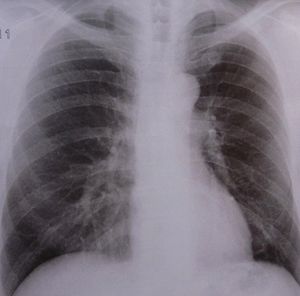

Sie sind hier: Startseite Nachrichten Gesundheit COPD: Neue Kriterien für Diagnose vorgestellt Lunge: COPD nimmt vielen Menschen den Atem.

Lunge: COPD nimmt vielen Menschen den Atem.